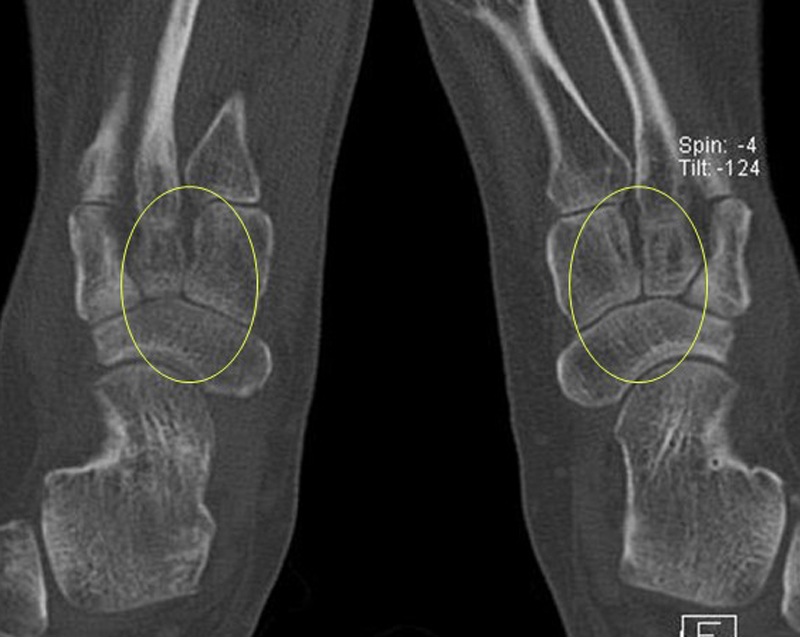

Die Abbildungen 4.2.a bis d zeigen den typischen Aspekt einer talacalcanearen Coalitio. Es besteht nur eine linksseitige, symptomatische Coalitio talocalcaneare (4.2.a und c); das 35 Tage zuvor angefertigte MRT zeigt keine auffälligen Signalveränderungen (4.2.b und d).

Abbildung 4.3. zeigt die Ursache für rechtsseitige Sprunggelenksbeschwerden bei einem Patienten mit talocalcanearen Coalitionen: nur die osteochondrale Läsion an der distalen rechten Tibia ist die Ursache des Schmerzes. Die bilateralen talocalcanearen Coalitionen sind asymptomatisch.